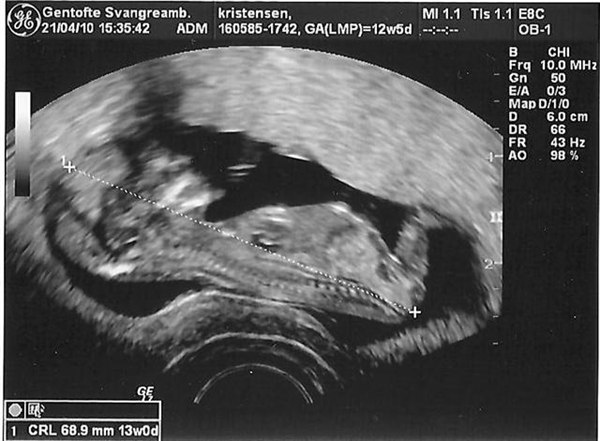

Så har vi været til scanning i dag og åååhhh... En fantastisk lille bebs

Risikoen for DS var 1:19500 ca så det var fine tal... Føler mig endelig rigtig gravid

Lige et lille billede...